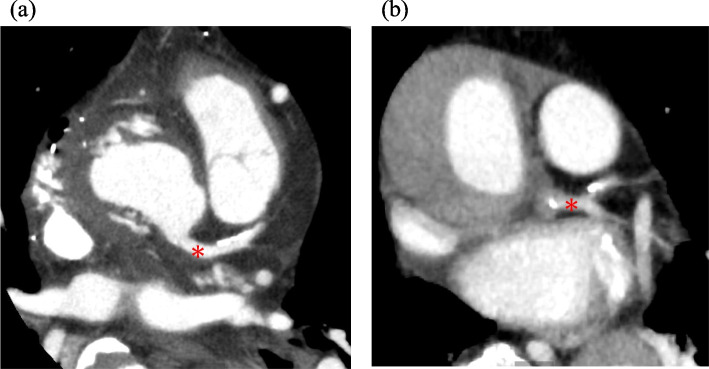

Case presentation: A 77-year-old man underwent emergency aortic arch replacement for acute type-A aortic dissection. Intraoperative transesophageal echocardiography (TEE) initially showed no coronary involvement. However, ST-segment elevation and new hypokinesia appeared post-repair. TEE identified progressive left main coronary artery stenosis. Coronary angiography confirmed severe stenosis, leading to urgent coronary artery bypass grafting. The patient recovered well and was discharged on postoperative day 33.